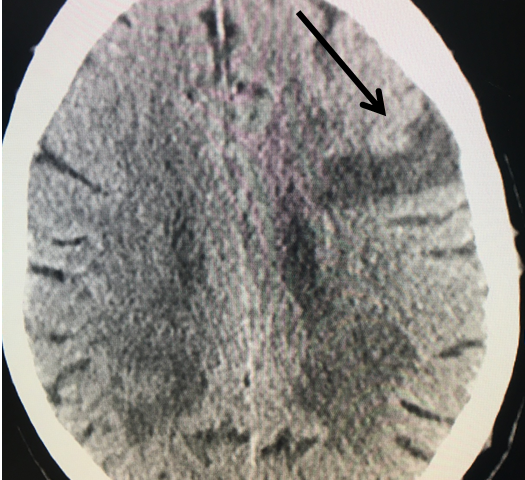

Figure 1.

This 77-year-old man with a history of stroke in 2013 presented to a small community hospital with aphasia upon awakening. Given the unclear timing of onset of his symptoms he was not deemed a candidate for intravenous thrombolytic. His NIHSS was 2 in the emergency room. He was admitted to the hospital where a CT (Figure 1) and CTA were performed showing a left frontal small infarct and severe extracranial carotid stenosis on the left. MRI could not be performed because of the patient’s pacemaker. Examination was significant for an awake gentleman with normal cranial nerve function and normal motor exam but significant expressive aphasia. Receptive aphasia was intact. He was placed on Aspirin.